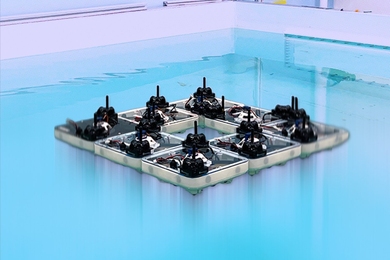

Researchers at MIT have developed injectable "mini livers" designed to temporarily take over essential liver functions, offering a potential new option for people with liver failure who are waiting for a transplant—or who aren't eligible for one at all.